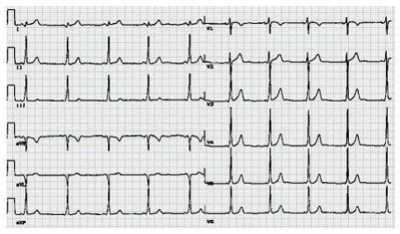

Taís, 31 anos, apresentou perda da consciência há algumas semanas. Diabetes mellitus desde os 8 anos. Há três meses, apresentou glicemia de jejum de 150 mg/dl, hemoglobina glicada (método HPLC) de 8,3; proteinúria (++). Seu médico sugeriu intensificação das atividades aeróbicas e ajustou as doses de insulina para 40 U de insulina NPH humana + 5 U de insulina regular, antes do desjejum e 10 U de NPH humana + 10 U de insulina regular 30 minutos antes do jantar. Após algumas semanas, os níveis de glicemia de jejum passaram a variar entre 70 e 90 mg/dl e a média nunca ultrapassou 150 mg/dl. Há três semanas, pela primeira vez na vida, apresentou palpitações, seguidas de perda da consciência. Recuperou-se rapidamente e foi levada à emergência, aonde chegou acordada, lúcida, sem lesões traumáticas e com leves abalos clônicos faciais. Foi medicada com glicose intravenosa. Posteriormente, teve 3 episódios de náuseas, sudorese, palpitação e borramento da visão, porém sem perda da consciência. Ganhou 3 kg nos últimos meses. Refere trabalhar muito, por vezes não consegue almoçar, fazendo “lanche ” e não tem condições de se automonitorar. Tinha crises de hipoglicemia na infância. Nega tabagismo, etilismo ou uso de drogas ilícitas. Peso: 72 kg. Sinais vitais: Tax = 36°C, PA = 126 x 16 mmHg, FC = 62 bpm, FR = 15 bpm. Fundoscopia normal. Exame físico sem alterações. Exames laboratoriais: Hemoglobina: 15,3 g/dl; leucometria: 5.500 mm³ (diferencial normal), ureia 20 mg/dl, creatinina 1,0 mg/dl, glicemia de jejum 66 mg/dl; colesterol total 160 mg/dl, HDL 45 mg/dl, LDL 100 mg/dl, triglicerídeos 120 mg/dl, hemoglobina glicada 8,0%; EAS normal; microalbuminúria = 42 mg/24 horas; cortisol sérico (60min após teste da cortrosina) 25 µ/dl. Nesta paciente, o uso do IECA para nefroproteção (VER IMAGEM):